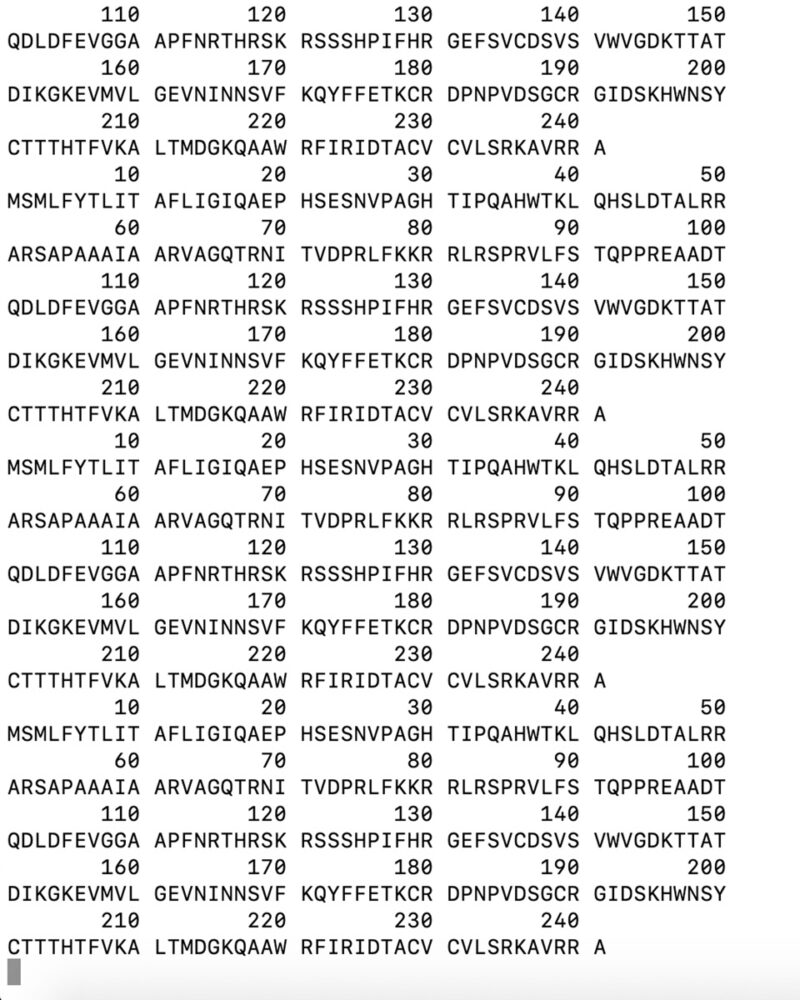

In neurobiology, a love relationship can be divided into two phases: falling in love and a bonding phase. The first is marked by the release of certain biochemical mediators such as dopamine and NGF. In this phase, the areas of the cortex that underlie desire, reward, and sexual excitement are active. Conversely, areas responsible for logic and reasoning are inactivated. The second phase is characterised by “bonding” and the passage to a phase of greater serenity and formation of the couple’s relationship.

This is how the idea of representing our love relationship was born, going to explore, with the method and scientific rigour, the neurobiological processes within our brain, and then repropose them to a possible viewer through some visual metaphors. We, therefore, produced and combined different types of images: from a small sculpture that recalls the molecular composition of dopamine to the neuroimaging of some sections of the brains of people in love, from the NGF sequence inserted into a computer terminal and screenshotted to a plant that alludes to the connection of the synapses of our nervous system.